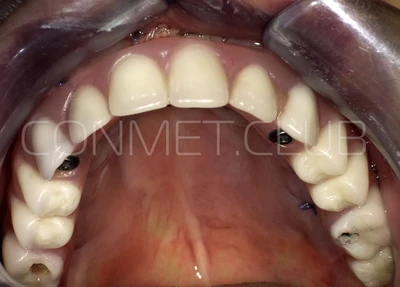

Подробное описание операции проведенной 4 апреля 2017 года

1. Пациенту было произведено МСКТ исследование нижней челюсти, с последующим созданием STL модели. В зуботехнической лаборатории был изготовлен восковой шаблон с искусственными зубами с учетом индивидуальных прикусных взаимоотношений (пока это делает зубной техник точно так же, как при изготовлении съемного пластиночного протеза).

2. После этого произвели компьютерное моделирование самого имплантата и фиксирующих элементов. Примечательно, что в абатментах, использовался отлично зарекомендовавший себя и проверенный десятилетиями интерфейс КОНМЕТ! В результате получили несколько специальных файлов, позволяющих не только сделать сам имлантат, но еще до операции изготовить и сами зубы. Данные файлы передали в изготовление на специальном 3D оборудовании.

Сама же операция длиться 20-50 минут в зависимости от количества утраченных зубов. В процессе этой операции, после проведенной местной анестезии, делается разрез на слизистой, она приподнимается и субпериостальный имплантат укладывается на кость. После этого рана фиксируется несколькими швами и все! Через 10-14 дней мягкие ткани срастаются и надкостница надежно удерживает имплантат на месте. Нет необходимости ждать несколько месяцев, как это бывает в случае с внутрикостными винтовыми имплантатами.

Новые, искусственные зубы фиксируются к этому имплантату стандартными, трансокклюзионными винтами на 1-14 день (в данном клиническом случае на 5 сутки) и по существу являются несъемными!